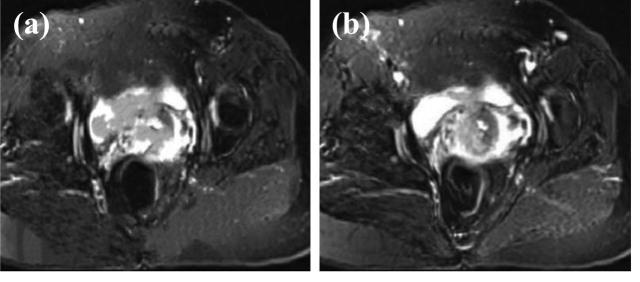

基于人工智能算法的磁共振多序列成像在宫颈癌分期诊断中的应用价值

Application value of artificial intelligence algorithm-based magnetic resonance multi-sequence imaging in staging diagnosis of cervical cancer.

The aim of this research is to explore the application value of Deep residual network model (DRN) for deep learning-based multi-sequence magnetic resonance imaging (MRI) in the staging diagnosis of cervical cancer (CC). This research included 90 patients diagnosed with CC between August 2019 and May 2021 at the hospital. After undergoing MRI examination, the clinical staging and surgical pathological staging of patients were conducted. The research then evaluated the results of clinical staging and MRI staging to assess their diagnostic accuracy and correlation. In the staging diagnosis of CC, the feature enhancement layer was added to the DRN model, and the MRI imaging features of CC were used to enhance the image information. The precision, specificity, and sensitivity of the constructed model were analyzed, and then the accuracy of clinical diagnosis staging and MRI staging were compared. As the model constructed DRN in this research was compared with convolutional neural network (CNN) and the classic deep neural network visual geometry group (VGG), the precision was 67.7, 84.9, and 93.6%, respectively. The sensitivity was 70.4, 82.5, and 91.2%, while the specificity was 68.5, 83.8, and 92.2%, respectively. The precision, sensitivity, and specificity of the model were remarkably higher than those of CNN and VGG models ( < 0.05). As the clinical staging and MRI staging of CC were compared, the diagnostic accuracy of MRI was 100%, while that of clinical diagnosis was 83.7%, showing a significant difference between them ( < 0.05). Multi-sequence MRI under intelligent algorithm had a high diagnostic rate for CC staging, deserving a good clinical application value.

摘要